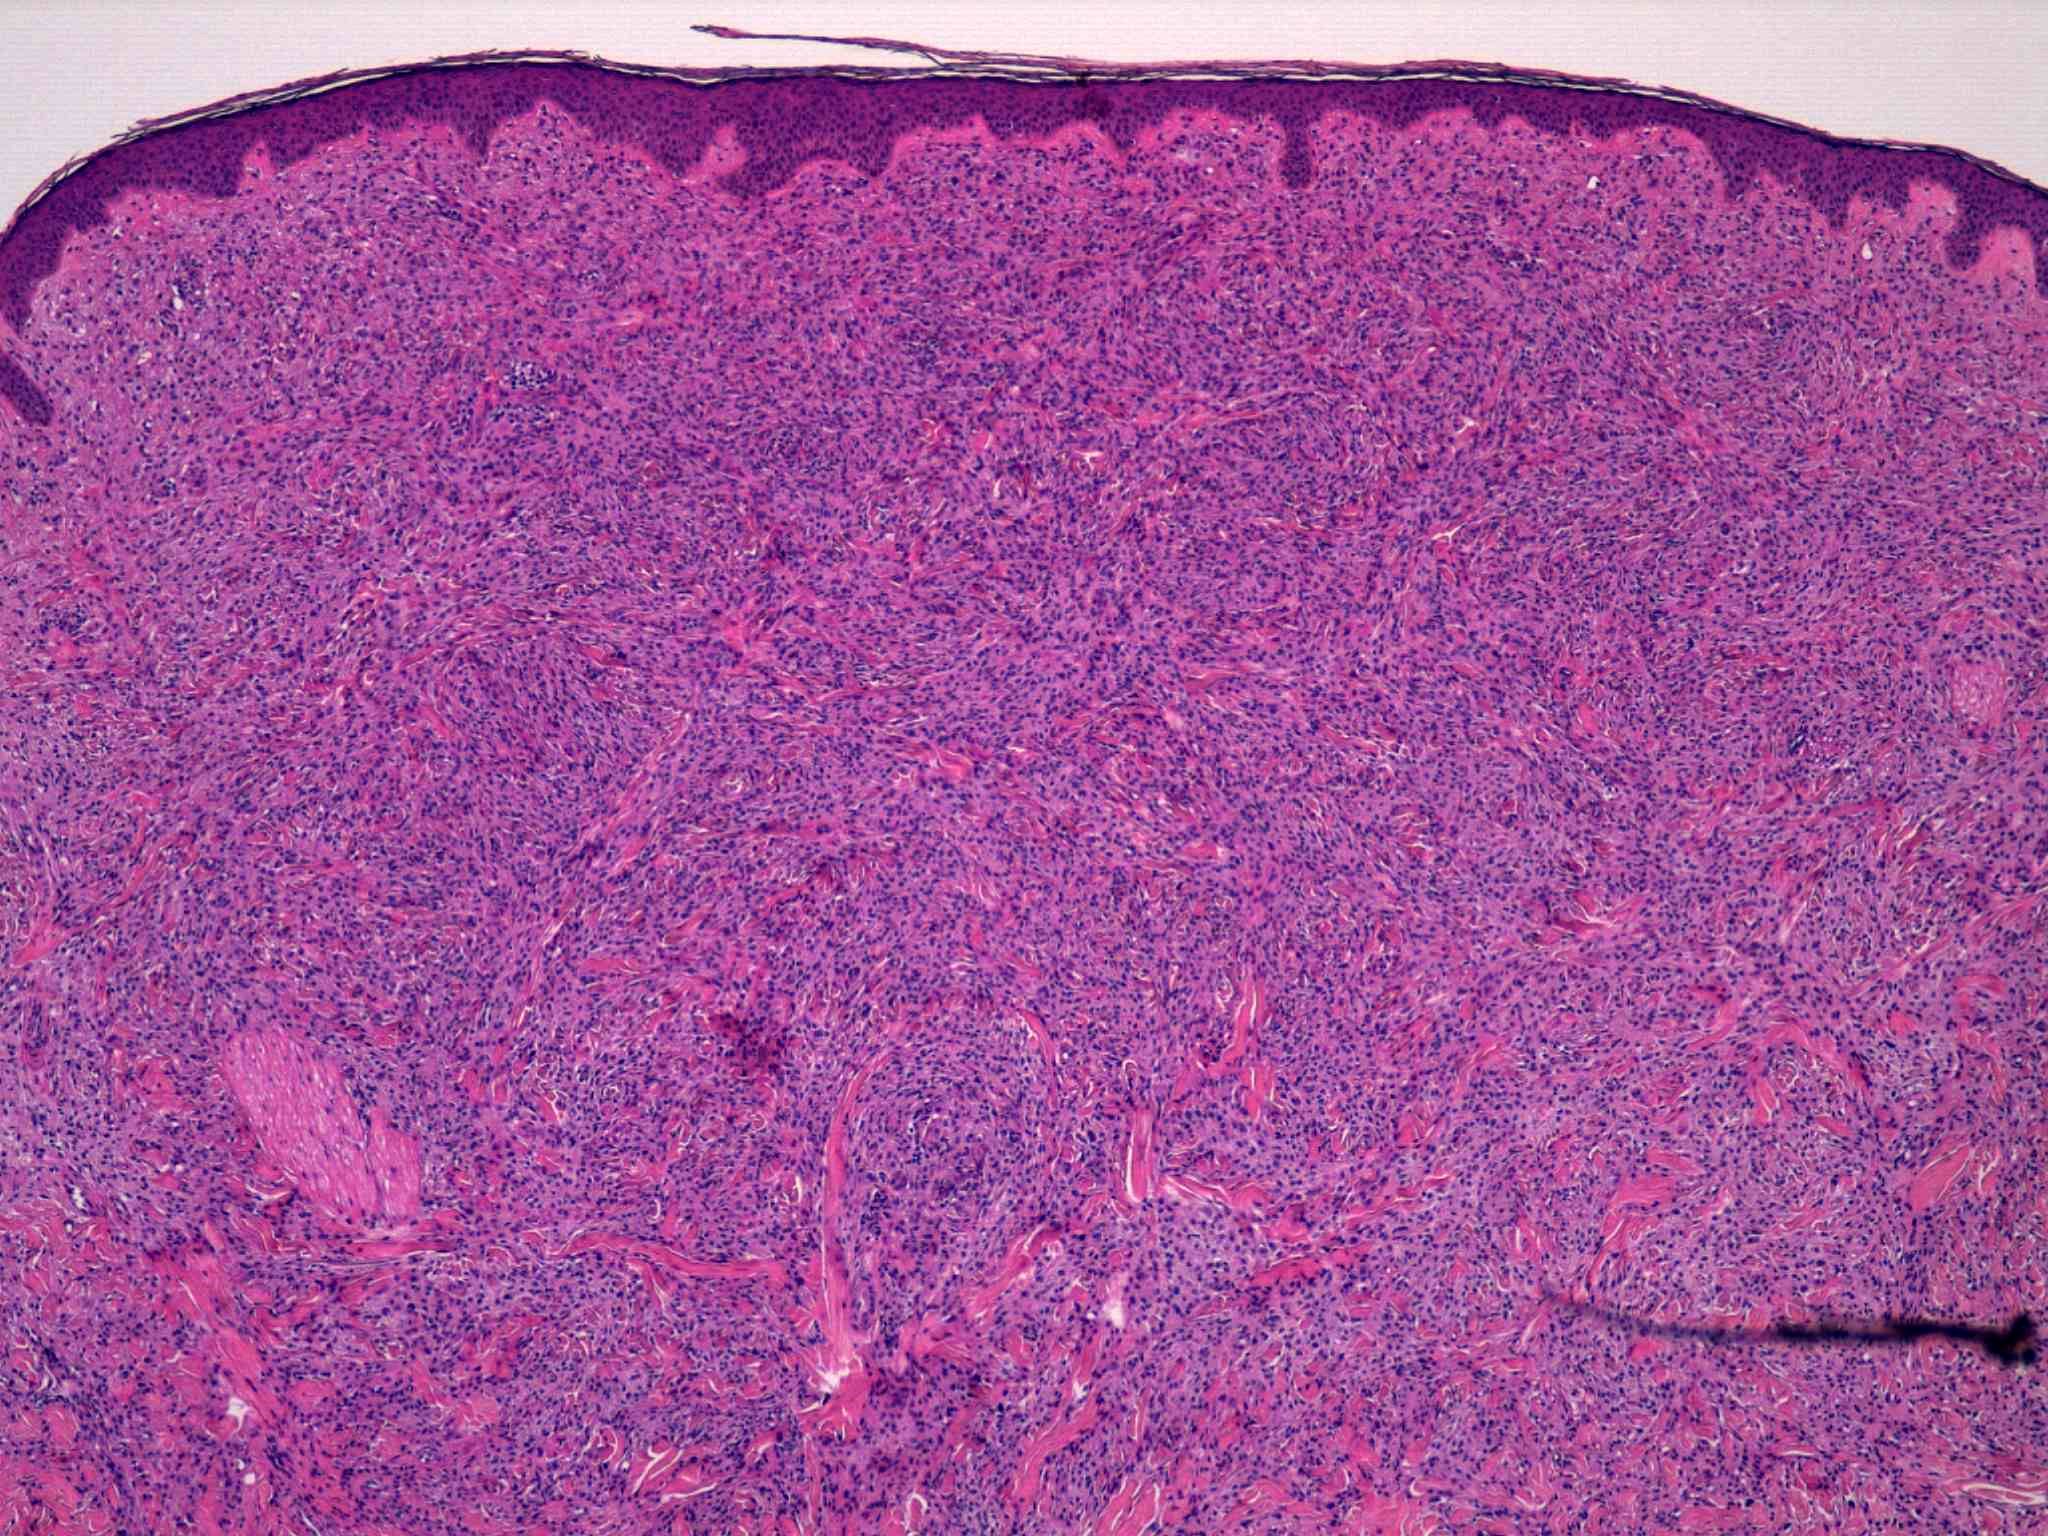

16 -- image_2011y10m04d_17h58m07s.jpg